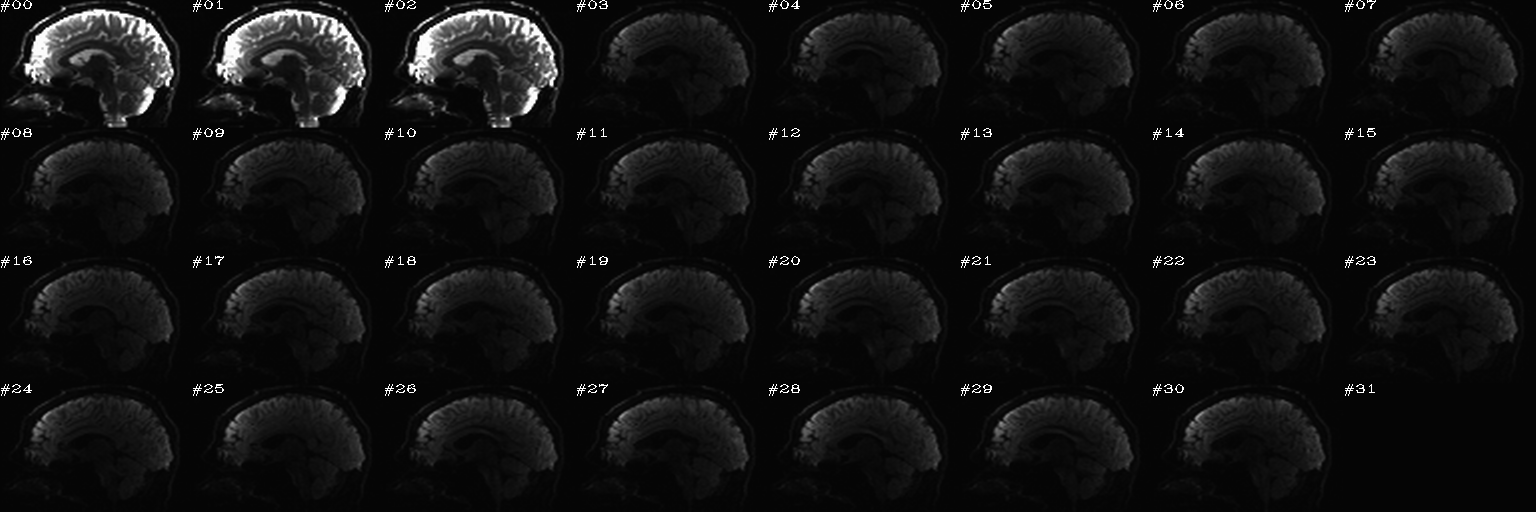

For slice viewing, I generally prefer using the sagittal view with separate scaling per volume. Generally, the presence of one or more bad slices is most readily apparent in these, IMHO.

Proc: A paired set of N DWIs with opposite phase encode directions (AP and PA); the following opens up an earlier-made set of sagittal views of each volume, with brightness scaled separately per slice, and one can click on bad volumes to add them to the list; then, in the second function call, the same list is reopened and the editing continues, since we want to form the union of bad volumes across the AP-PA pair of dsets. When all is said and done here, the main thing we will want from this is the string selector of the list of good volumes to keep, which will be called dwi_sel_both_goods.txt:

After the first function has started and some clicks have been made (described in caption):

After the first function has finished and the second function has just executed– no clicks made yet:

After some clicks have been made during the execution of the second function: